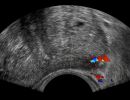

- Peripheral Prostate Zone: The exam can detect focal lesions, such as neoplasms, in the peripheral zone of the prostate.

- Examination: The exam begins with a Lower Abdominal Ultrasound (suprapubic) and continues with the transrectal exam after urination. The transrectal ultrasound is performed using a special probe inserted into the rectum through the anal sphincter. This method provides a comprehensive evaluation of the prostate's morphology.